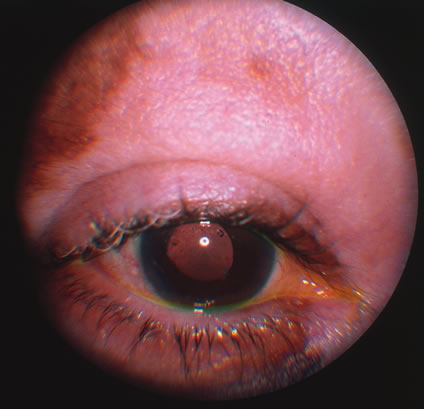

Involvement by VZV of the first division of the trigeminal nerve is referred to as herpes zoster ophthalmicus regardless of whether the eye is inflamed (Fig. 5). Eighty-five percent of patients with cutaneous eruptions on the side of the tip or midportion of the nose (Hutchinson's sign) will have ocular involvement. Varicella zoster virus can cause blepharitis, canaliculitis, episcleritis, scleritis, conjunctivitis, keratitis, iridocyclitis, uveitis, retinal vasculitis, retinitis, choroiditis, and optic neuritis. Cataracts and glaucoma are late complications related to the uveitis and long-term use of topical corticosteroid therapy.

Fig. 5. Facial involvement in a case of zoster. Note the characteristic strict segmental distribution of the lesions.